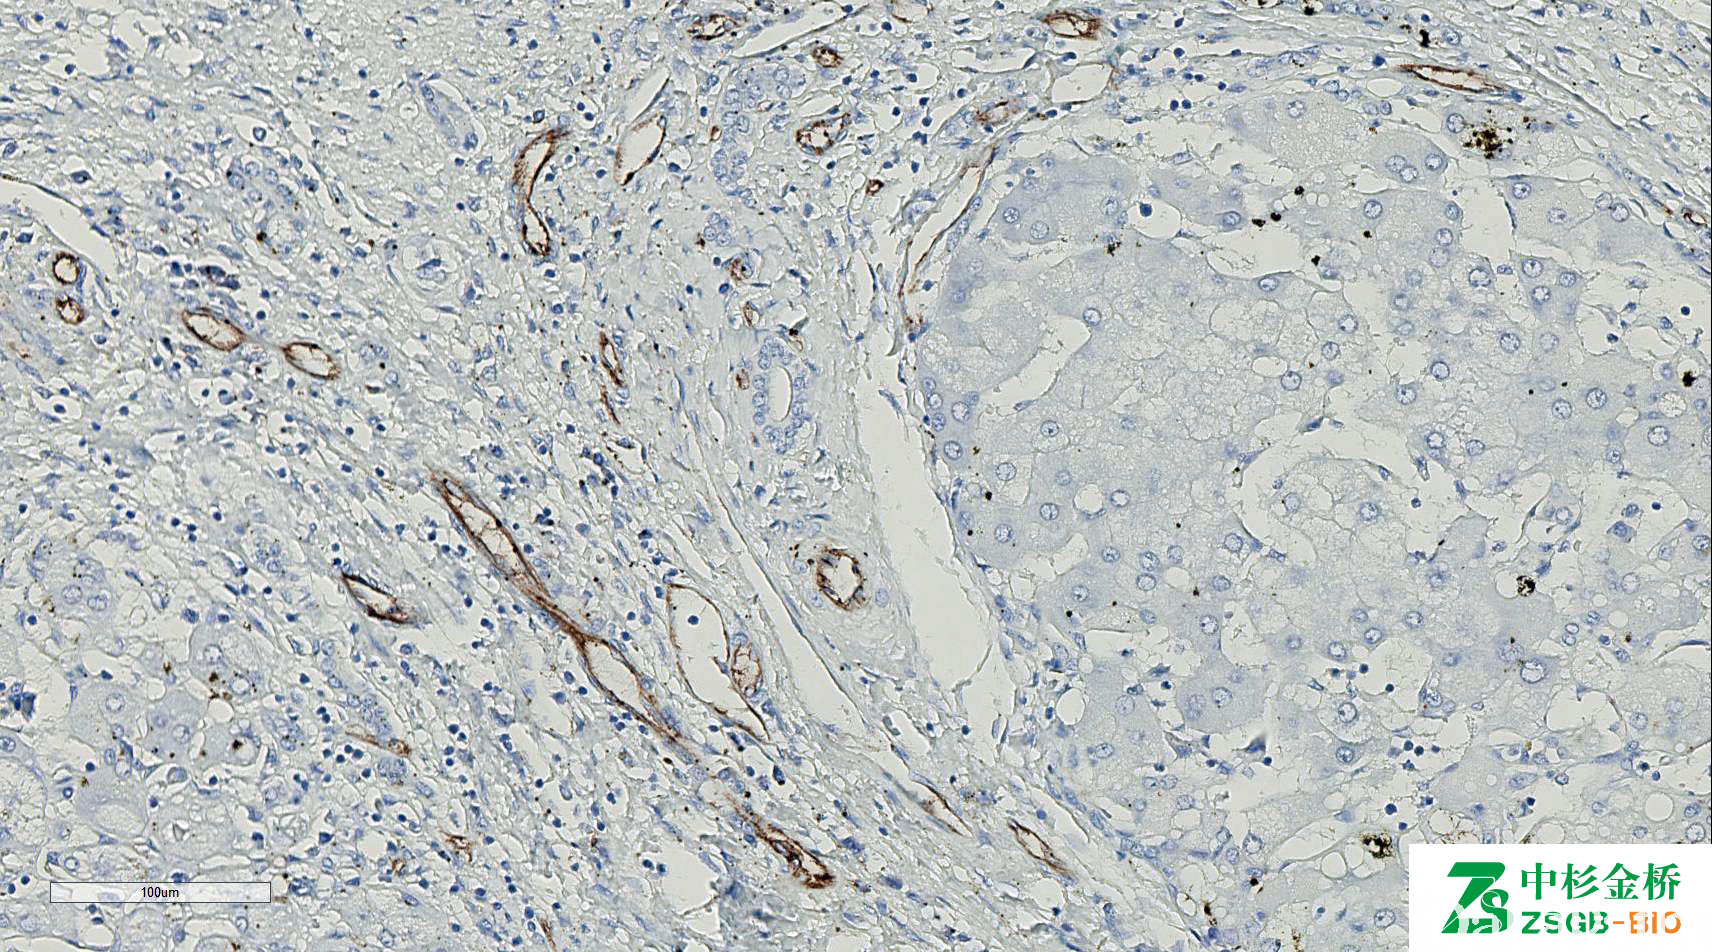

CD31

别名: PECAM-1

血小板内皮细胞黏附分子,是一种膜糖蛋白。属免疫球蛋白超家族,在所有连续性内皮表达,但不连续的血窦内皮不表达。巨核细胞、血小板、髓细胞、NK 细胞和部分 T、B 细胞也表达。

血管内皮细胞肿瘤的诊断与鉴别诊断(比 CD34、VIII 因子更敏感、更特异)。